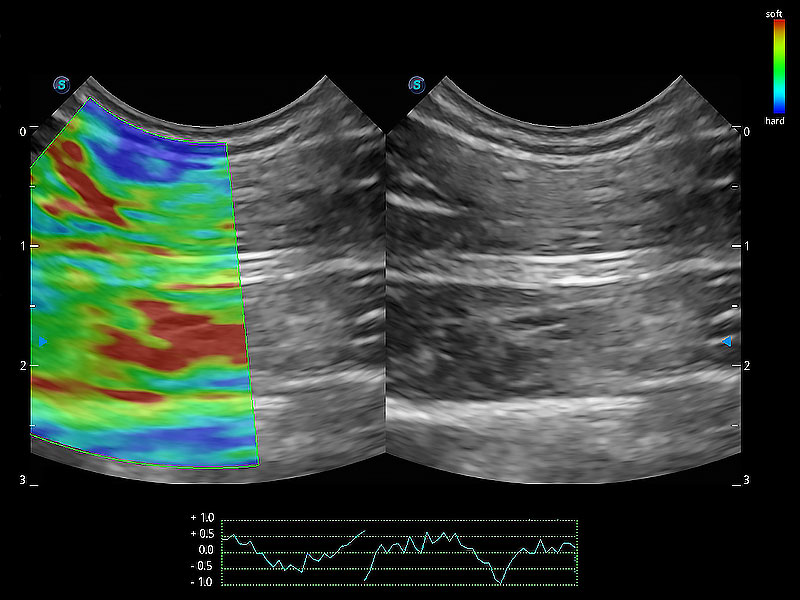

操作簡便,無需高頻度外力作用即可真實(shí)反映組織的形變,快速評估腫瘤良惡性。